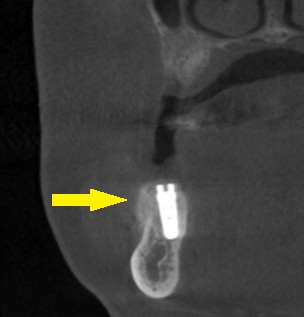

ご了承いただけましたので、本日、2本のインプラント埋入と、骨造成術を行いました。

下の写真3段目が手術後のCTです。